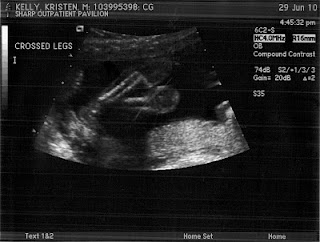

Here are a few shots from the ultrasound showing her little face, spine, and crossed legs - she's a modest lil one!